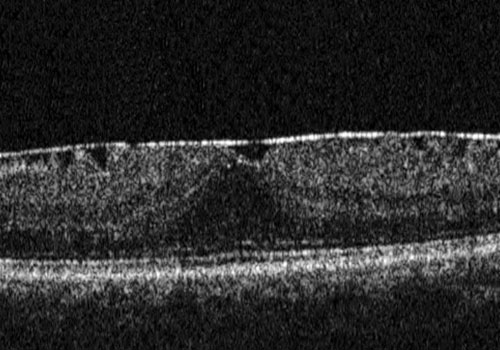

La membrana epiretinica è una membrana fibrocellulare che si forma sulla superficie retinica interna per la proliferazione di cellule gliali migrate attraverso rotture della membrana limitante interna. Il risultato è rappresentato da un “raggrinzimento” della porzione centrale della retina, da cui deriva una distorsione delle immagini e un calo visivo, che può peggiorare nel tempo.

Nei casi più gravi la membrana tende a contrarsi e a stirare la superficie retinica. Il paziente inizia a lamentarsi di una visione distorta (metamorfopsia) e di un variabile grado di diminuzione dell'acuità visiva.